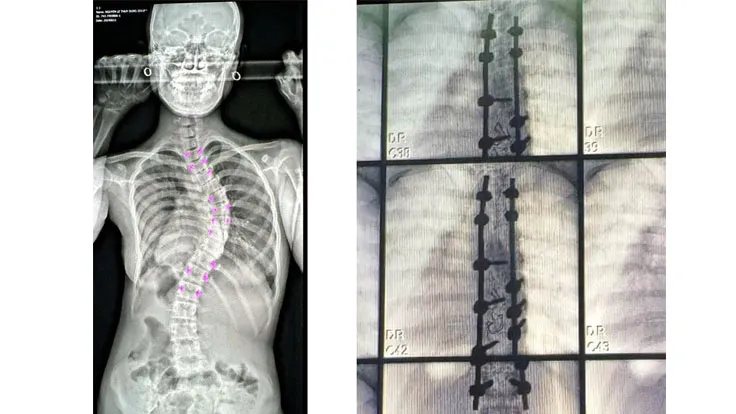

Bệnh nhân N.L.T.D., 13 tuổi (tỉnh Bình Thuận) bị cong vẹo cột sống bên phải gần 2 năm, khiến người bệnh sinh hoạt khó khăn, tự ti về ngoại hình, đặc biệt trong tuổi dậy thì.

Qua thăm khám, các bác sĩ quyết định thực hiện phẫu thuật nắn chỉnh khối cong vẹo cột sống bằng hệ thống nẹp vít và các dụng cụ chỉnh hình chuyên dụng, đảm bảo thần kinh toàn vẹn cho bệnh nhân. Sau 3 ngày phẫu thuật, bệnh nhân phục hồi sức khỏe tốt, không tổn thương về thần kinh, có thể đi lại nhẹ nhàng và tiếp tục tập phục hồi chức năng.

Trường hợp bệnh nhân B.L.D. (12 tuổi, ngụ tại TPHCM) phát hiện cột sống cong bất thường từ sau khi dậy thì. Khối cong vẹo lưng đã ảnh hưởng đến vẻ ngoài, dáng đi khiến bệnh nhân tự ti, ngại tiếp xúc. Sau 2 ngày, bệnh nhân đã tự đi đứng tốt. Theo bác sĩ BS-CKI Trần Dạ Vương, Khoa Ngoại Thần Kinh, Bệnh viện Vạn Phúc City, vẹo cột sống có thể xảy ra ở mọi độ tuổi. Tuổi dễ phát triển nhanh nhất là dậy thì từ 10 – 17 tuổi (nhất là quanh tuổi có kinh nguyệt) ở các bé gái và 12 – 18 tuổi ở các trẻ trai.